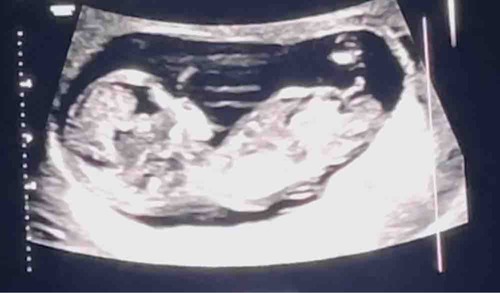

Hey hey! Zie je iets aan mijn echo? Is van 12 weken en 5 dgen 😅

Hier kan je het niet zo goed op zien